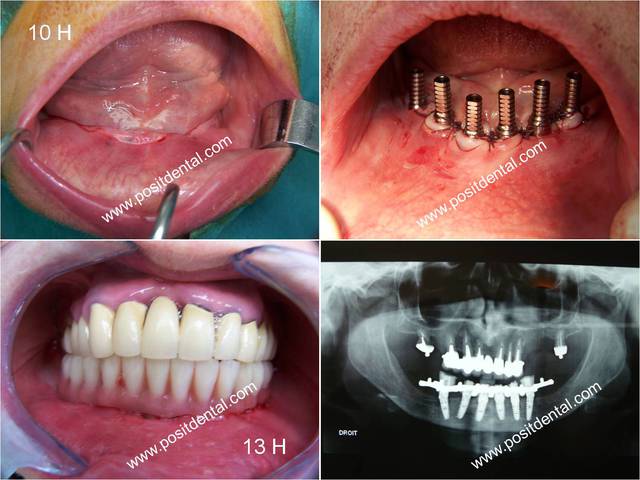

le cas clinique précédent sont des ALPHABIO et celui ci des MIS

je te rassure hervel ce sont des piliers provisoires pour prothèse transvissée, les voici solidaire au bridge sur pilotis